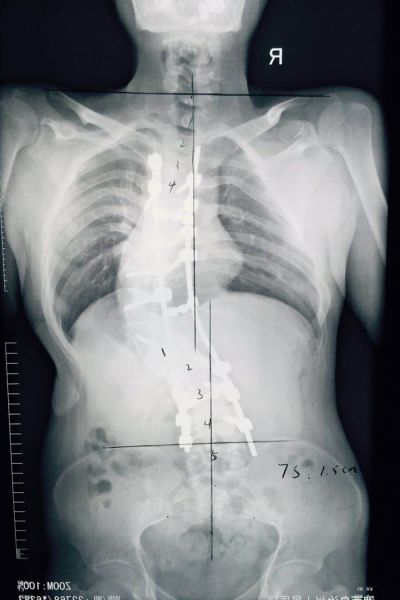

患者于4月21日在全麻下行脊柱后路固定、截骨、矫形、植骨融合术,手术历时12个小时,过程基本顺利,完整达到手术目的。后经过一个多月的积极神经康复锻炼,患者目前基本恢复。患者妈妈激动的说:“孩子长高了,现在和我一样高了,背也直了!”。而且经过术后评估检测,患者伤口一级愈合,身高增长7cm,剃刀背高度下降8cm,双肩等高,躯干已基本平衡,脊柱畸形得到满意矫正,目前患者及家属已经满意出院。